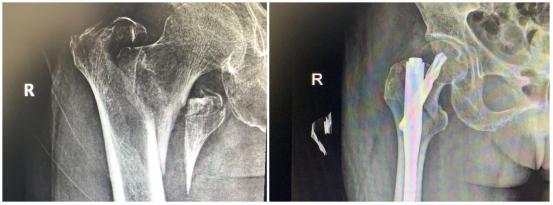

年前 , 蔡奶奶在家摔了一跤 , 右侧股骨剧烈疼痛 , 不能走路 , 无法动弹 。 检查发现老人右侧股骨粗隆间骨折 , 当时老人拒绝治疗 , 回家卧床后每况愈下 。 家人不忍心看着老人这么痛苦 , 了解到该院骨科擅长老年性骨折治疗 , 于是带着老人来到该院鼓山路院区骨科就诊 。 来院后 , 患者诊断为右股骨粗隆间粉碎骨折 , 并伴有右下肢深静脉血栓、褥疮、肺部感染等并发症 , 情况非常危险 , 此类骨折又称为“死亡骨折” 。 据了解 , “死亡骨折”是指老年人的髋部骨折 , 常常是股骨粗隆间骨折和股骨颈骨折 , 其中骨折后卧床引起的并发症会导致死亡 , 死亡率高达40% , 又称人生最后一次骨折 。

此类手术风险大 , 医生在告知患者家属手术风险、术后康复、抢救方案等情况后 , 家属打消了顾虑 , 决定尽快给老人家安排手术 , 摆脱病痛折磨 。 同时 , 麻醉科为老人制定了个性化的麻醉方案 。 王斌手术团队给患者制定了微创手术方案 , 通过三个小孔来进行固定 , 避免了大的手术切口 , 整个手术过程仅仅耗时50分钟 , 出血量50ml左右 。

【骨折|94岁老人遭遇“死亡骨折”,南京市江宁医院骨科微创手术显神功】患者术后第二天就下地站立行走 , X线显示骨折对位好 , 复查下肢静脉B超提示少许肌间静脉血栓 。 在专科医生的康复指导下 , 患者褥疮、肺部感染也很快消失了 。 术后第7天 , 患者康复出院 。

截至目前 , 南京市江宁医院骨科团队已成功开展近千例“死亡骨折”微创手术 。 这种手术避免了切开复位骨折 , 减少出血 , 无需肌肉的切开 , 对组织破坏极其微小 , 固定牢靠 , 稳定性强 , 患者恢复快 , 不用担心移位 。